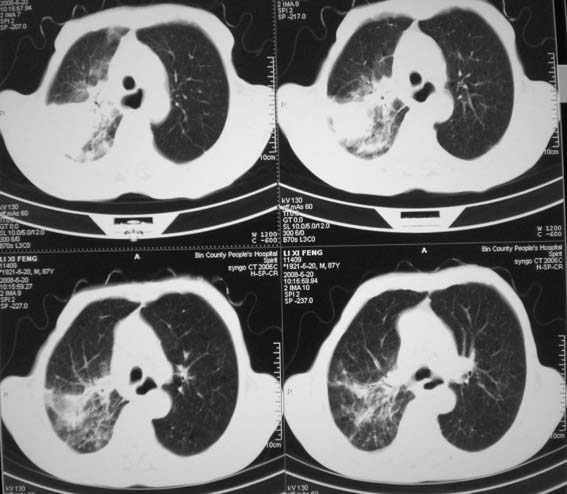

男,87岁,咳嗽、发烧、有黄痰,胸片示肺结核。

右肺上叶尖后段片状不规则致密影,密度欠均匀,相邻胸膜肥厚,纵隔内见多发肿大、钙化淋巴结,考虑为结核,部分坏死

有低密度坏死灶;结合痰检。